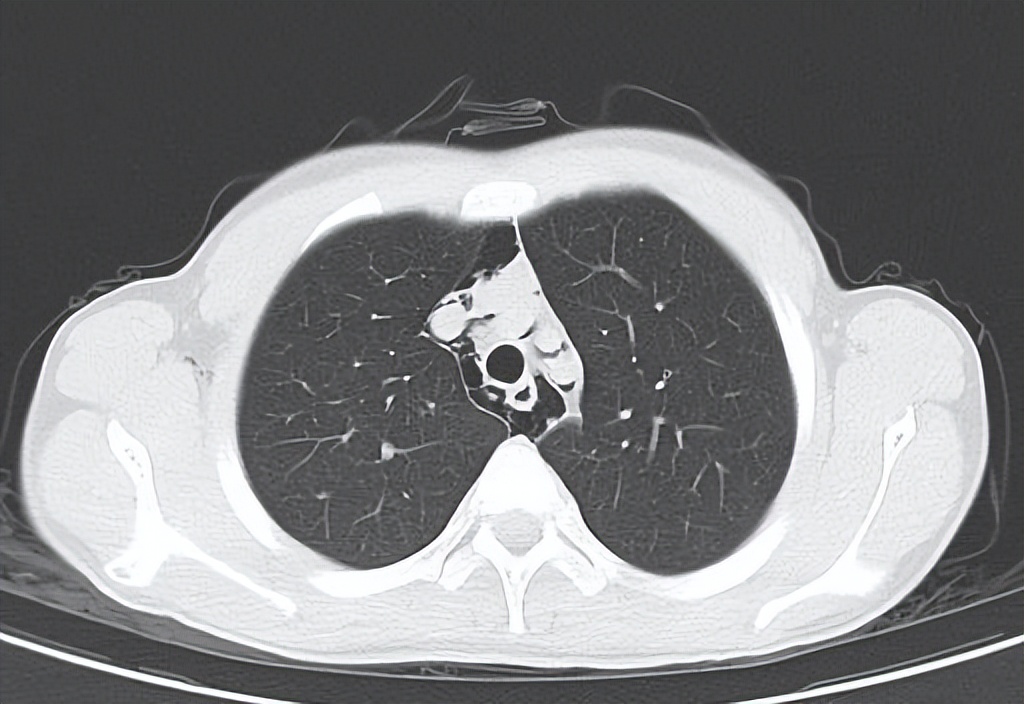

“小福,去查个胸部CT吧,有可能纵隔气肿了。”急诊医生没把话说得太满。

胸部CT检查:纵隔及颈部气肿,右侧胸壁软组织积气。